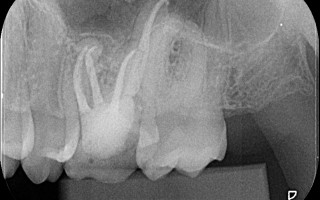

Reintervenção Endodôntica em Molar Superior com Curvatura

Reintervenção Endodôntica em Molar Superior com Curvaturas apicais em todas as raízes. O caso foi preparado com a hibridização com Reciproc R25 e M2 30, 35, 40 e 45.